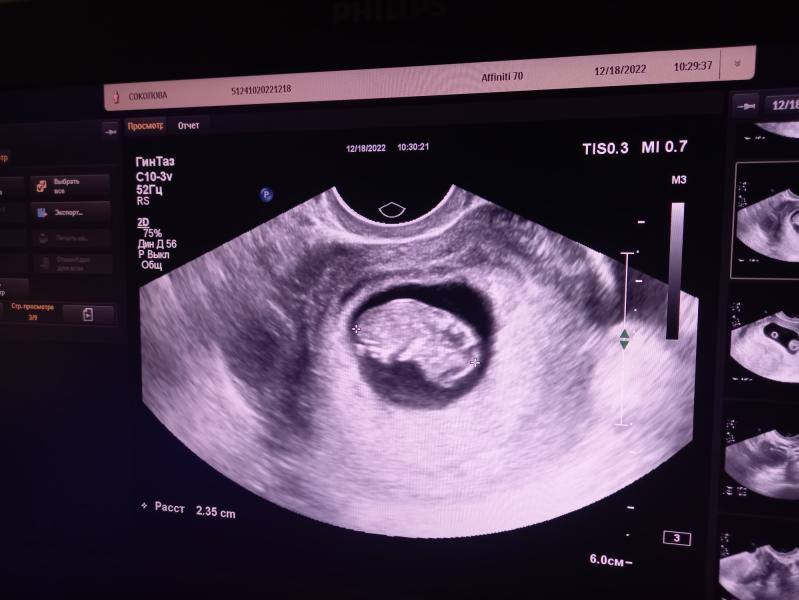

post image